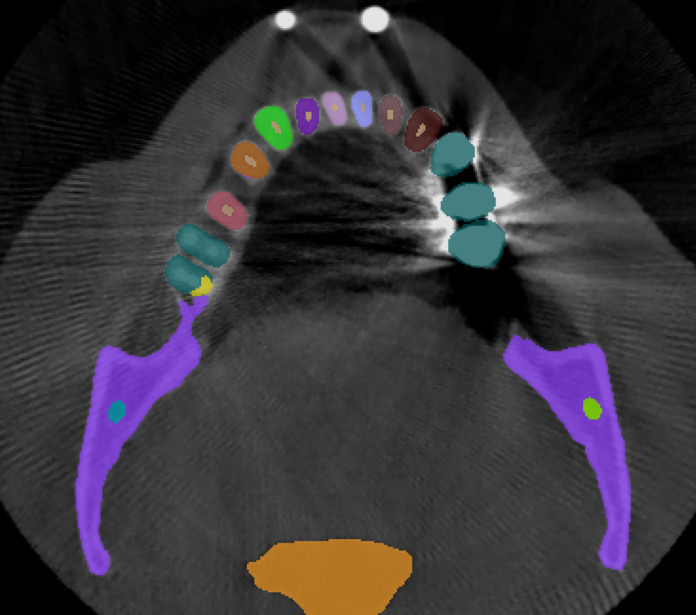

3.2 Qualitative Results

Fig.˜2 visualizes the qualitative comparison between the ground truth and our model’s predictions of the scans with the highest and lowest Dice score in the validation set, in the top and bottom rows, respectively. We observe that in most cases, U-Mamba2 produces precise segmentation predictions, showcasing the effectiveness of incorporating dental domain knowledge into the model design. Furthermore, we observe that U-Mamba2 can accurately localize the three tiny structures (ILN), producing visually acceptable segmentations. In the worst-case scenario, although the scan is imperfect due to image artifacts caused by metallic objects, false positives are primarily confined around the image edge or confusion between the actual tooth and the crown or implant, underscoring U-Mamba2’s robustness under noisy conditions.